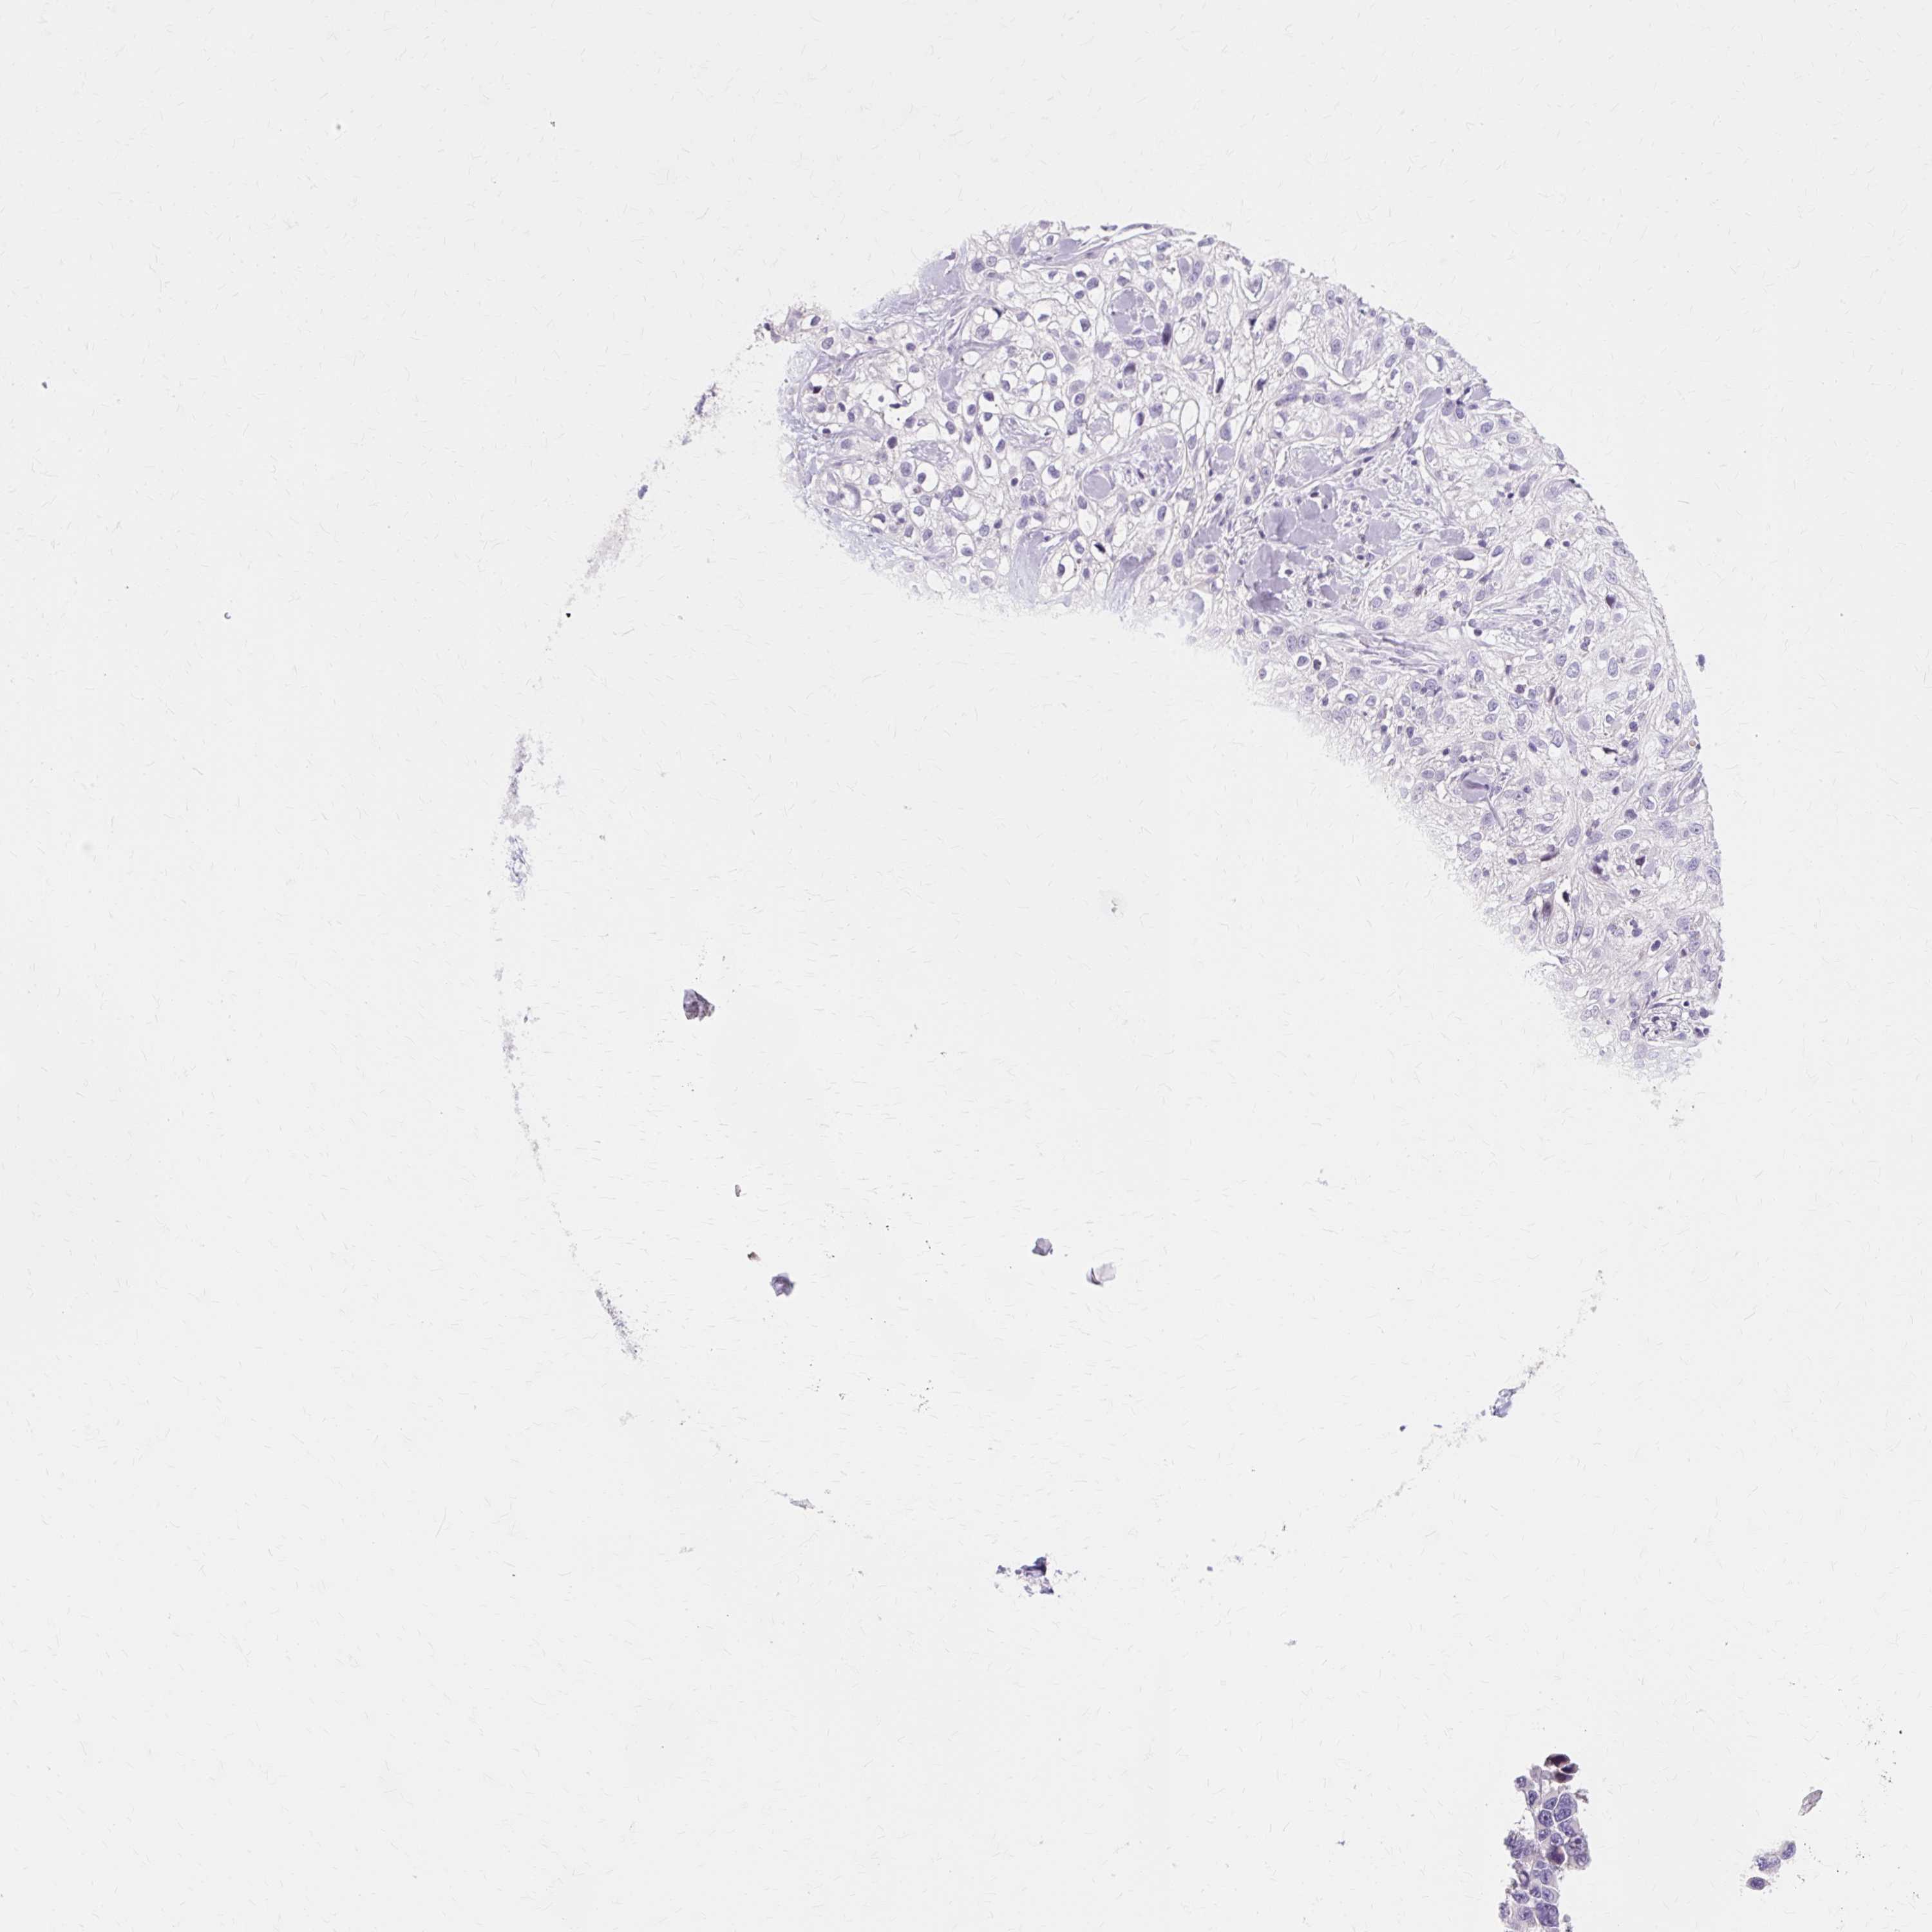

CANCER SKIN CANCER Show tissue menu

Basal cell and squamous cell cancer

SKIN CANCER - Protein expressioni

A mouse-over function shows sample information and annotation data. Click on an image to view it in a full screen mode. Samples can be filtered based on level of antibody staining by selecting one or several of the following categories: high, medium, low and not detected. The assay and annotation is described here.

Each image is clickable and will lead to virtual microscopy that enables deeper exploration of all samples and also displays staining intensity scores, fraction scores and subcellular localization as well as patient and tissue information for each sample.

Antibody HPA054669

Staining

High

Medium

Low

Not detected

Intensity

Strong

Moderate

Weak

Negative

Quantity

>75%

75%-25%

<25%

None

Location

Nuclear

Cytoplasmic/membranous

Cytoplasmic/membranous,nuclear

Basal cell carcinoma

Squamous cell carcinoma, NOS